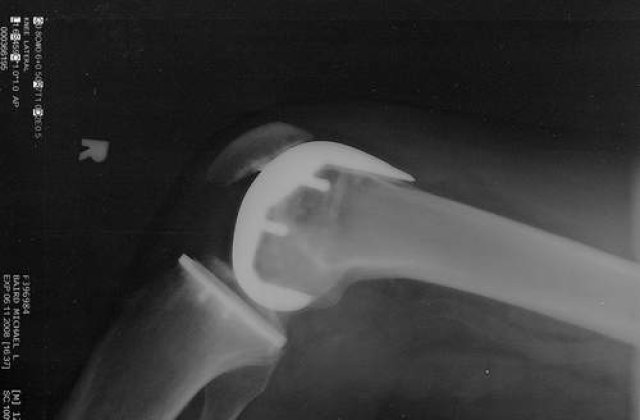

Artroza este o afectiune in care cartilajul ce protejeaza si inveleste suprafetele articulare se deterioreaza. Oasele, nemaifiind separate de cartilaj, incep sa se erodeze, ceea ce duce la lezarea tesutului si a osului subiacent, cauzand dureri articulare.